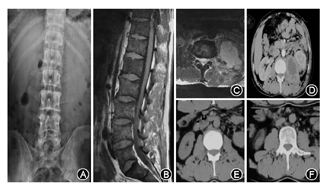

4例X线片表现异常,其中2例胸部X片可见肺部陈旧性钙化灶。腰椎正侧位X线片可见一侧腰大肌影模糊或增宽、局部饱满或隆起,脓肿较大时腰大肌影不清,偶可见斑片或长条状钙化。(2)CT:本组9例经CT扫描,表现为椎旁局限于腰大肌的圆形、类圆形边界清楚的低密度囊性占位,单囊或多囊表现,内部可见点状、条状、片状钙化。(3)MRI:本组13例均行MRI扫描,表现为椎旁局限于腰大肌的圆形、类圆形边界清楚的囊性占位,纵径多超过2个椎节范围。T1WI像呈低或略低信号,T2WI像呈高或中高信号,边界清楚、整齐,部分囊内散在点状或条状低信号。脓肿壁T1WI像呈略长T1信号,较囊内脓液信号略高,T2WI像呈略短信号,较脓液信号略低,增强后囊壁强化明显,但中央坏死液化区无明显强化。(4)B型超声检查:本组6例行B型超声检查表现病侧腰大肌内见长条状和(或)不规则的液性暗区,内壁模糊不规整,暗区内见团状或带状强回声光带和密集的细光点回声,有漂浮征象,伴后方回声增强,探头加压可稍变形。(5)同位素扫描:本组4例完成同位素骨扫描,排除其他部位的感染所引起的继发感染。

11例患者行病变侧腹膜后入路结核脓肿切开病灶清除术,平均引流脓液约130 ml,术中平均出血150 ml,彻底病灶清除后局部放置链霉素2 g。6例脓腔较大的患者术后留置引流管,其中5例引流3~7 d后拔出,1例因术后引流量较多,于45 d后拔出,1例单房性脓肿行B超引导下穿刺引流,术中引流量30 ml,术后留置引流管于14 d后拔出。所有患者术后均继续口服联合抗结核药物及保肝治疗6~12个月(图1)。